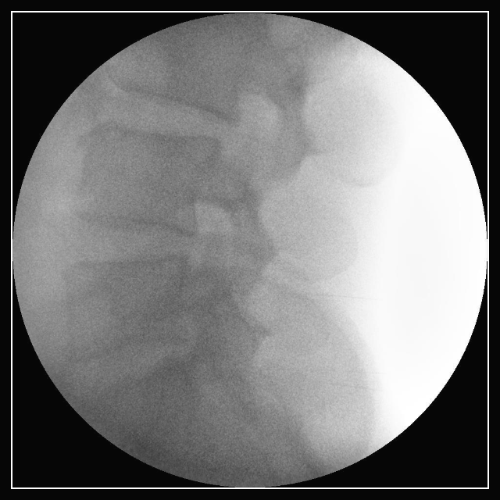

① 신경근 차단술은 척추신경이 척추나 디스크 등 주변 조직으로부터 압박을 받아 허리나 하지에 통증이 발생할 경우 신경근 차단술이 고려될 수 있습니다. 통증이 발생한 부위에 약물을 주사하여 통증 신경 부위를 차단함으로써 요통 증상을 완화시킵니다.

허리 주사 치료 및 신경 차단술은 허리 통증을 줄이고 관리하기 위한 치료 방법 중 하나입니다.

허리 주사 치료는 직접적으로 신경이나 관절에 약물을 주입하여 통증을 완화시키는 방법입니다.

신경 차단술은 신경의 전기적 신호를 차단하여 통증을 완화시키는 방법입니다.

이 방법은 국소 마취제를 사용하여 신경이나 관절 주위에 약물을 주입하거나, 레이저나 온열치료 등으로 신경을 파괴하는 방법을 사용합니다.